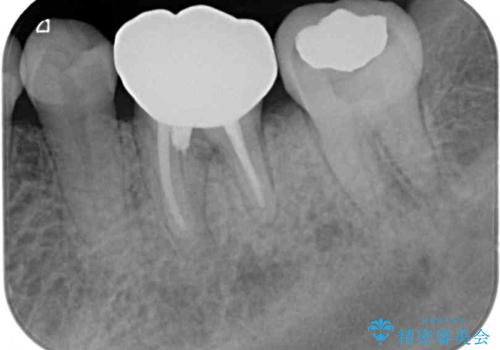

根管治療を終えた後には、今まで気になっていた痛みが消え、快適に日常生活を送れるようになりました。

痛みが取れるとともに、気になっていた大きな銀歯も自然なセラミックとなり、患者様には大変満足していただけました。